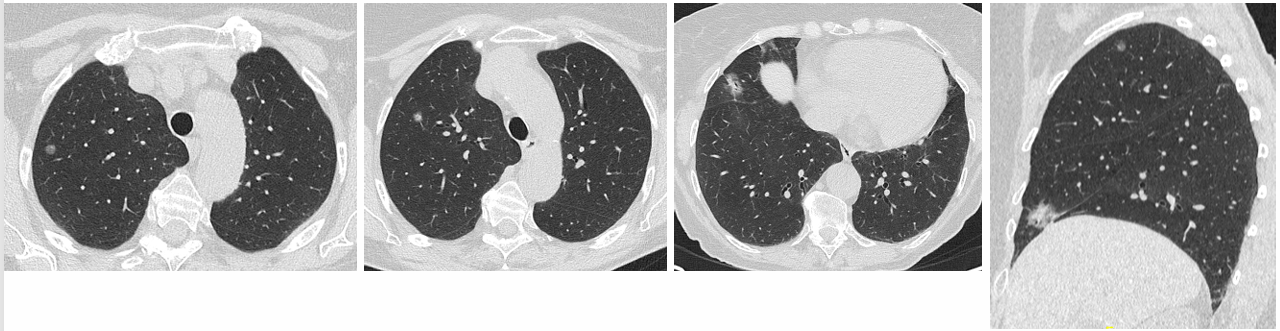

2024年11月,首次CT检查发现多个微小肺结节。多学科团队(MDT)讨论后决定,对患者进行3个月的CT随访。

2025年1月,随访CT:与2024年11月的CT对比,既往描述的肺结节未见明显变化,呈持续存在状态。主要病灶包括:未见纵隔或肺门淋巴结肿大。右肺上叶亚实性结节,8mm,含4mm实性成分。右肺上叶磨玻璃结节,7mm。右肺上叶前段磨玻璃结节,4mm。右肺中叶亚实性结节,19mm,含10mm实性成分(最大病灶)。右肺下叶叶间裂旁磨玻璃结节,4mm。未见纵隔或肺门淋巴结肿大。

1c7da45b-90c4-4729-853c-1b414294788d.png